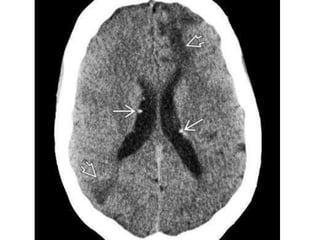

• #30 NECT scan shows additional calcified SENs , wedge-shaped hypodensities characteristic of the WM lesions in TSC

• #31 CECT scan shows enhancement adjacent to the foramen of Monro, suspicious for subependymal giant cell astrocytoma.